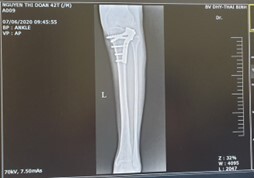

The diagnosis was based primarily on patient history, reported postoperative tightness, persistent paresthesia, signs of contracture, muscle fibrosis, and foot deformity. Radiographs at 6 months showed the fracture had healed (Figure 3).